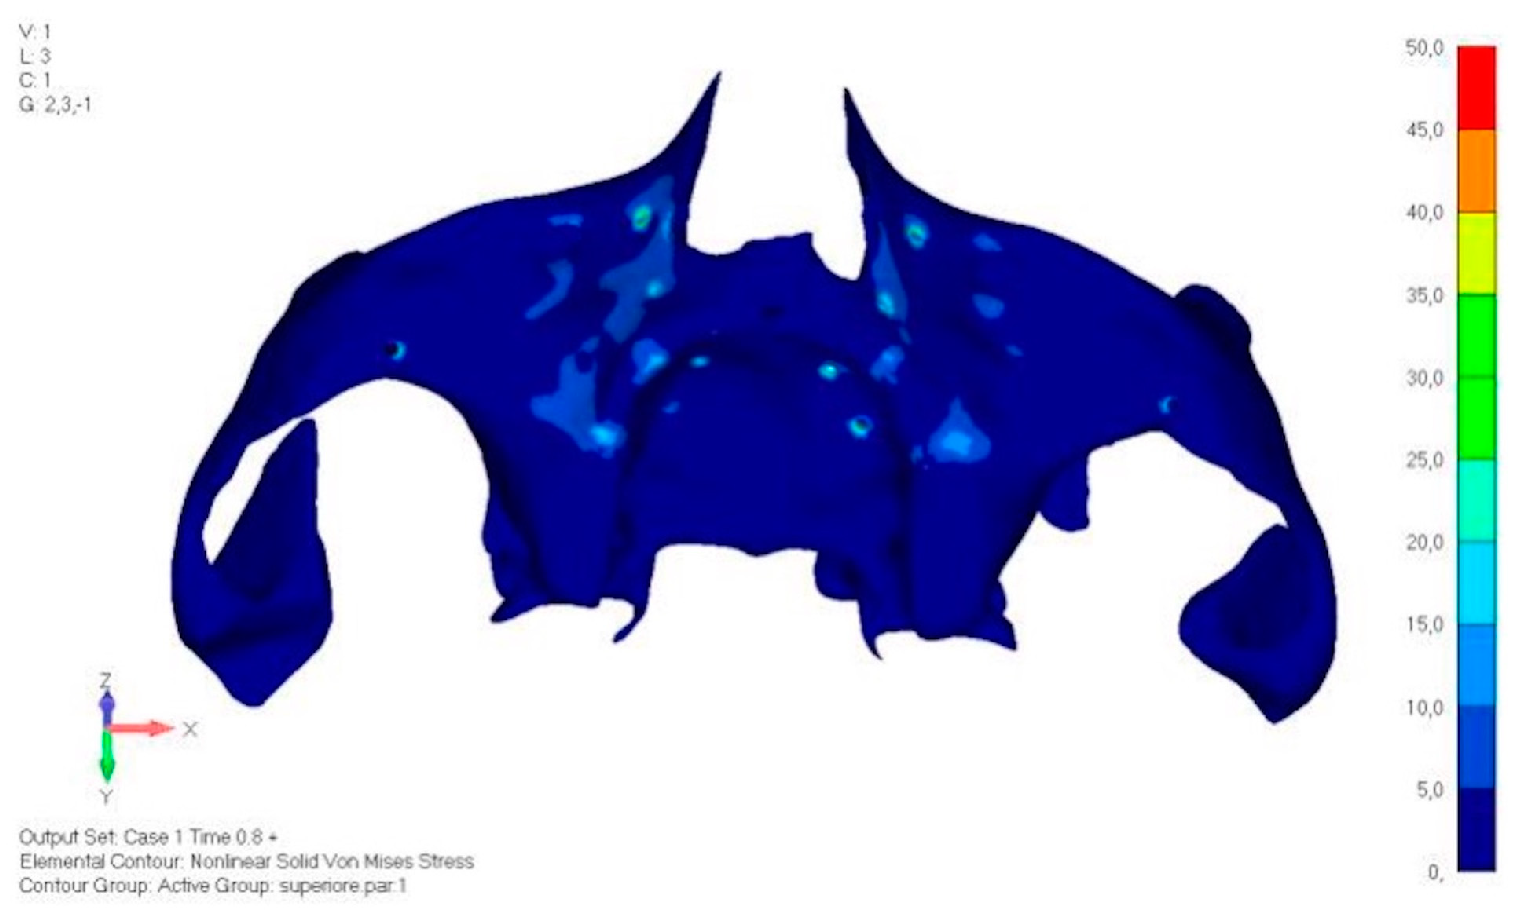

- Model V0. From the analysis of Model V0, it emerged that the most critical situation is related to load configuration 3 (Figure 5a,b), which represents a load applied to the anterior right side. The least critical situations are load configurations 1 and 2 (Figure 6 and Figure 7), corresponding to a load distributed across the entire dentition and a load distributed only on the posterior teeth, respectively. Regarding the stress values observed, no critical issues were identified with the juxta-osseous implant. In load configuration 3, the stresses are below the breaking limits of titanium laser melting: peak stresses of 500 MPa are reached only in very localized areas of the implant.

- Model V1. Added posterior screws, reducing stress on anterior parts and achieving more balanced distribution. The addition of the posterior screw has certainly alleviated the load on the palatal screw, which was excessively stressed in the previous model (Figure 8). The screw now experiencing the most stress is the posterior screw: compared to the previous case, only part of the hole shows a stress exceeding 50 MPa, and the area affected by this stress is therefore much more contained (Figure 9a,b).